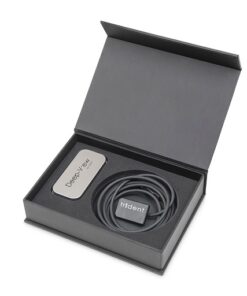

Radiovisiógrafo RVG i-SENSOR H2

Características principales

- Alto nivel de claridad y detalle en la radiografía digital.

- Efecto de imagen más claro, de modo que se pueda encontrar fácilmente la sutil bifurcación del ápice de la raíz.

- Sensor delgado, que permite mejores radiografías de mordida y una adquisición de mordida vertical simplificada.

- Durable y confiable. Diseñado para evitar cualquier tipo de daño en su uso diario.

- Experiencia de peso ultraligero y protección IP68 con la posibilidad de sumergir el sensor en líquido desinfectante.